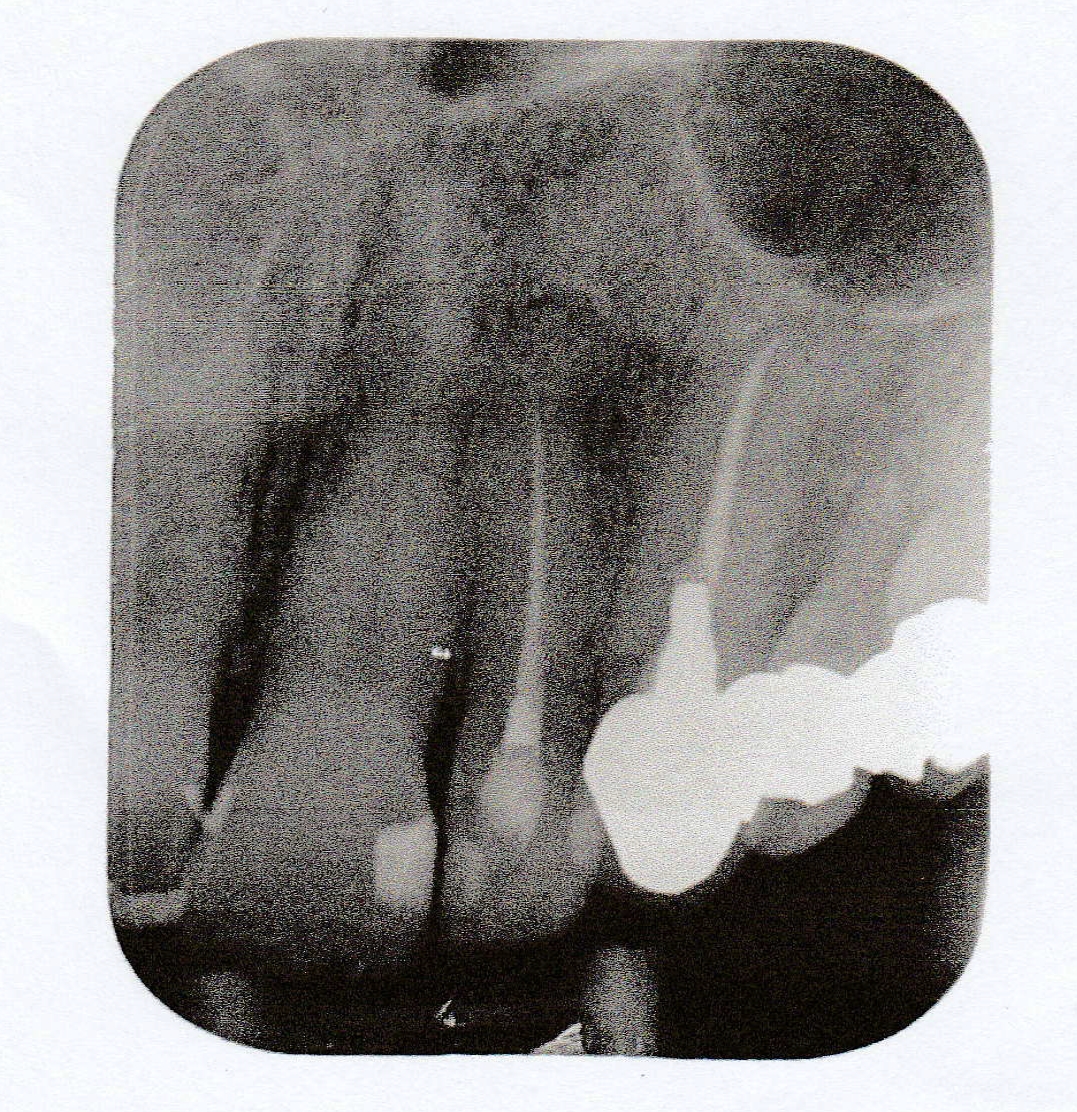

Boven hoektand met kroon zit klein bultje. Op foto: persisterende ontsteking. Over een halve week apexresectie 23 door kaakchirurg.

Kan ontsteking wortelpunt doorlopen tot in de kaakholte? Soms komt er hele vieze troep via mijn keel en neus naar buiten (groen en bloederig slijm met korst, heel vies ruikend). Voor die tijd heb ik meer pijn, als de rommel eruit is, wordt de pijn minder- dan zeurt het een beetje).